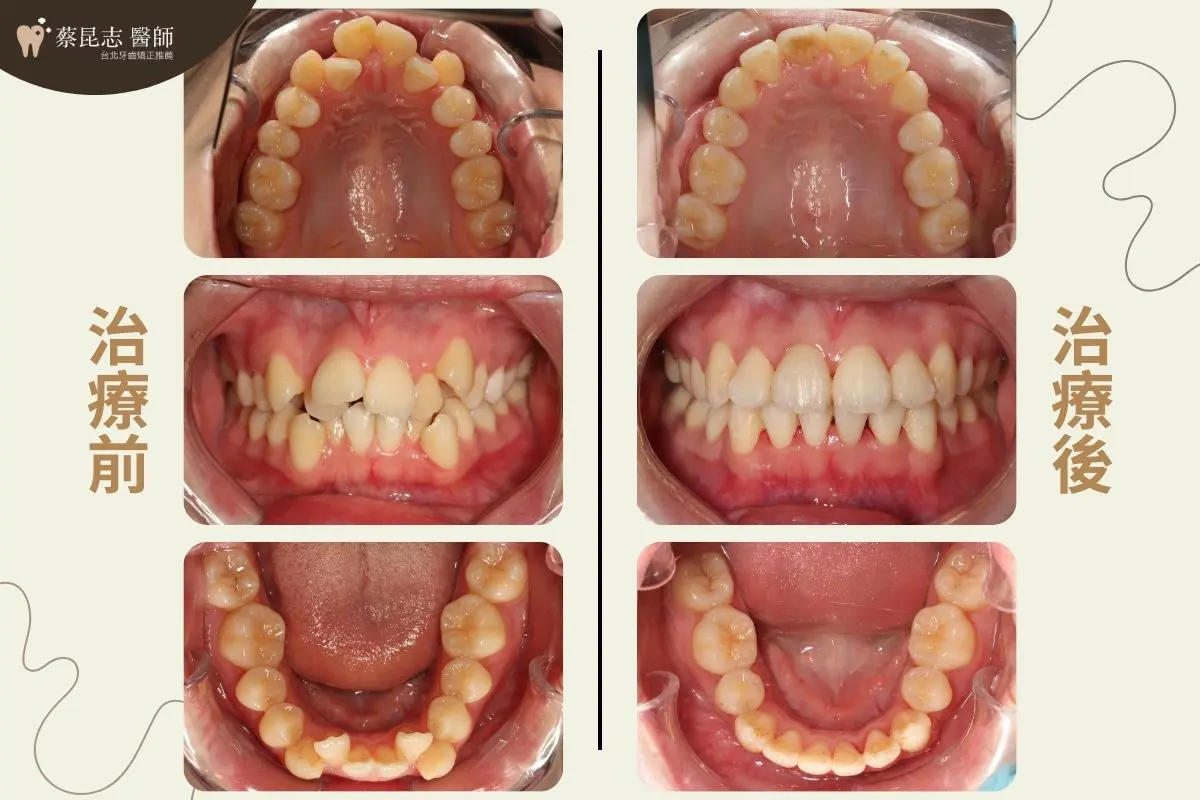

治療前可以見到因為上下顎前牙嚴重擁擠、上顎高位犬齒,造成笑容的不美觀。

又因為上顎前牙過於外暴、上下顎前牙水平距離差距過大,所以側面輪廓上唇過於外凸,和咬合不正。